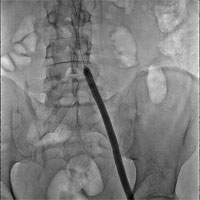

В Пироговском Центре впервые в России имплантирован венозный стент нового поколения VENOVO (Bard, США), выполнена реканализация и стентирование глубоких подвздошных вен у пациента с синдромом нижней полой вены, развившегося после билатерального илио-феморального тромбоза. Операцию выполнил заведующий отделением рентгенохирургических методов диагностики и лечения профессор А.Г. Виллер.

До настоящего времени эндоваскулярная хирургия посттромботической болезни была частично лимитирована невозможностью имплантации существующих венозных саморасширяемых стентов в функционально подвижных зонах — паховых и подколенных сгибах. Баллонная ангиопластика без стентирования в этих зонах всегда имеет повышенный риск повторной окклюзии. Внедрение в клиническую практику стентов, резистентных к дополнительному механическому воздействию, существенно повышает эффективность эндоваскулярной хирургии посттромботической болезни, позволяет восстанавливать проходимость и подвздошных и бедренных вен.